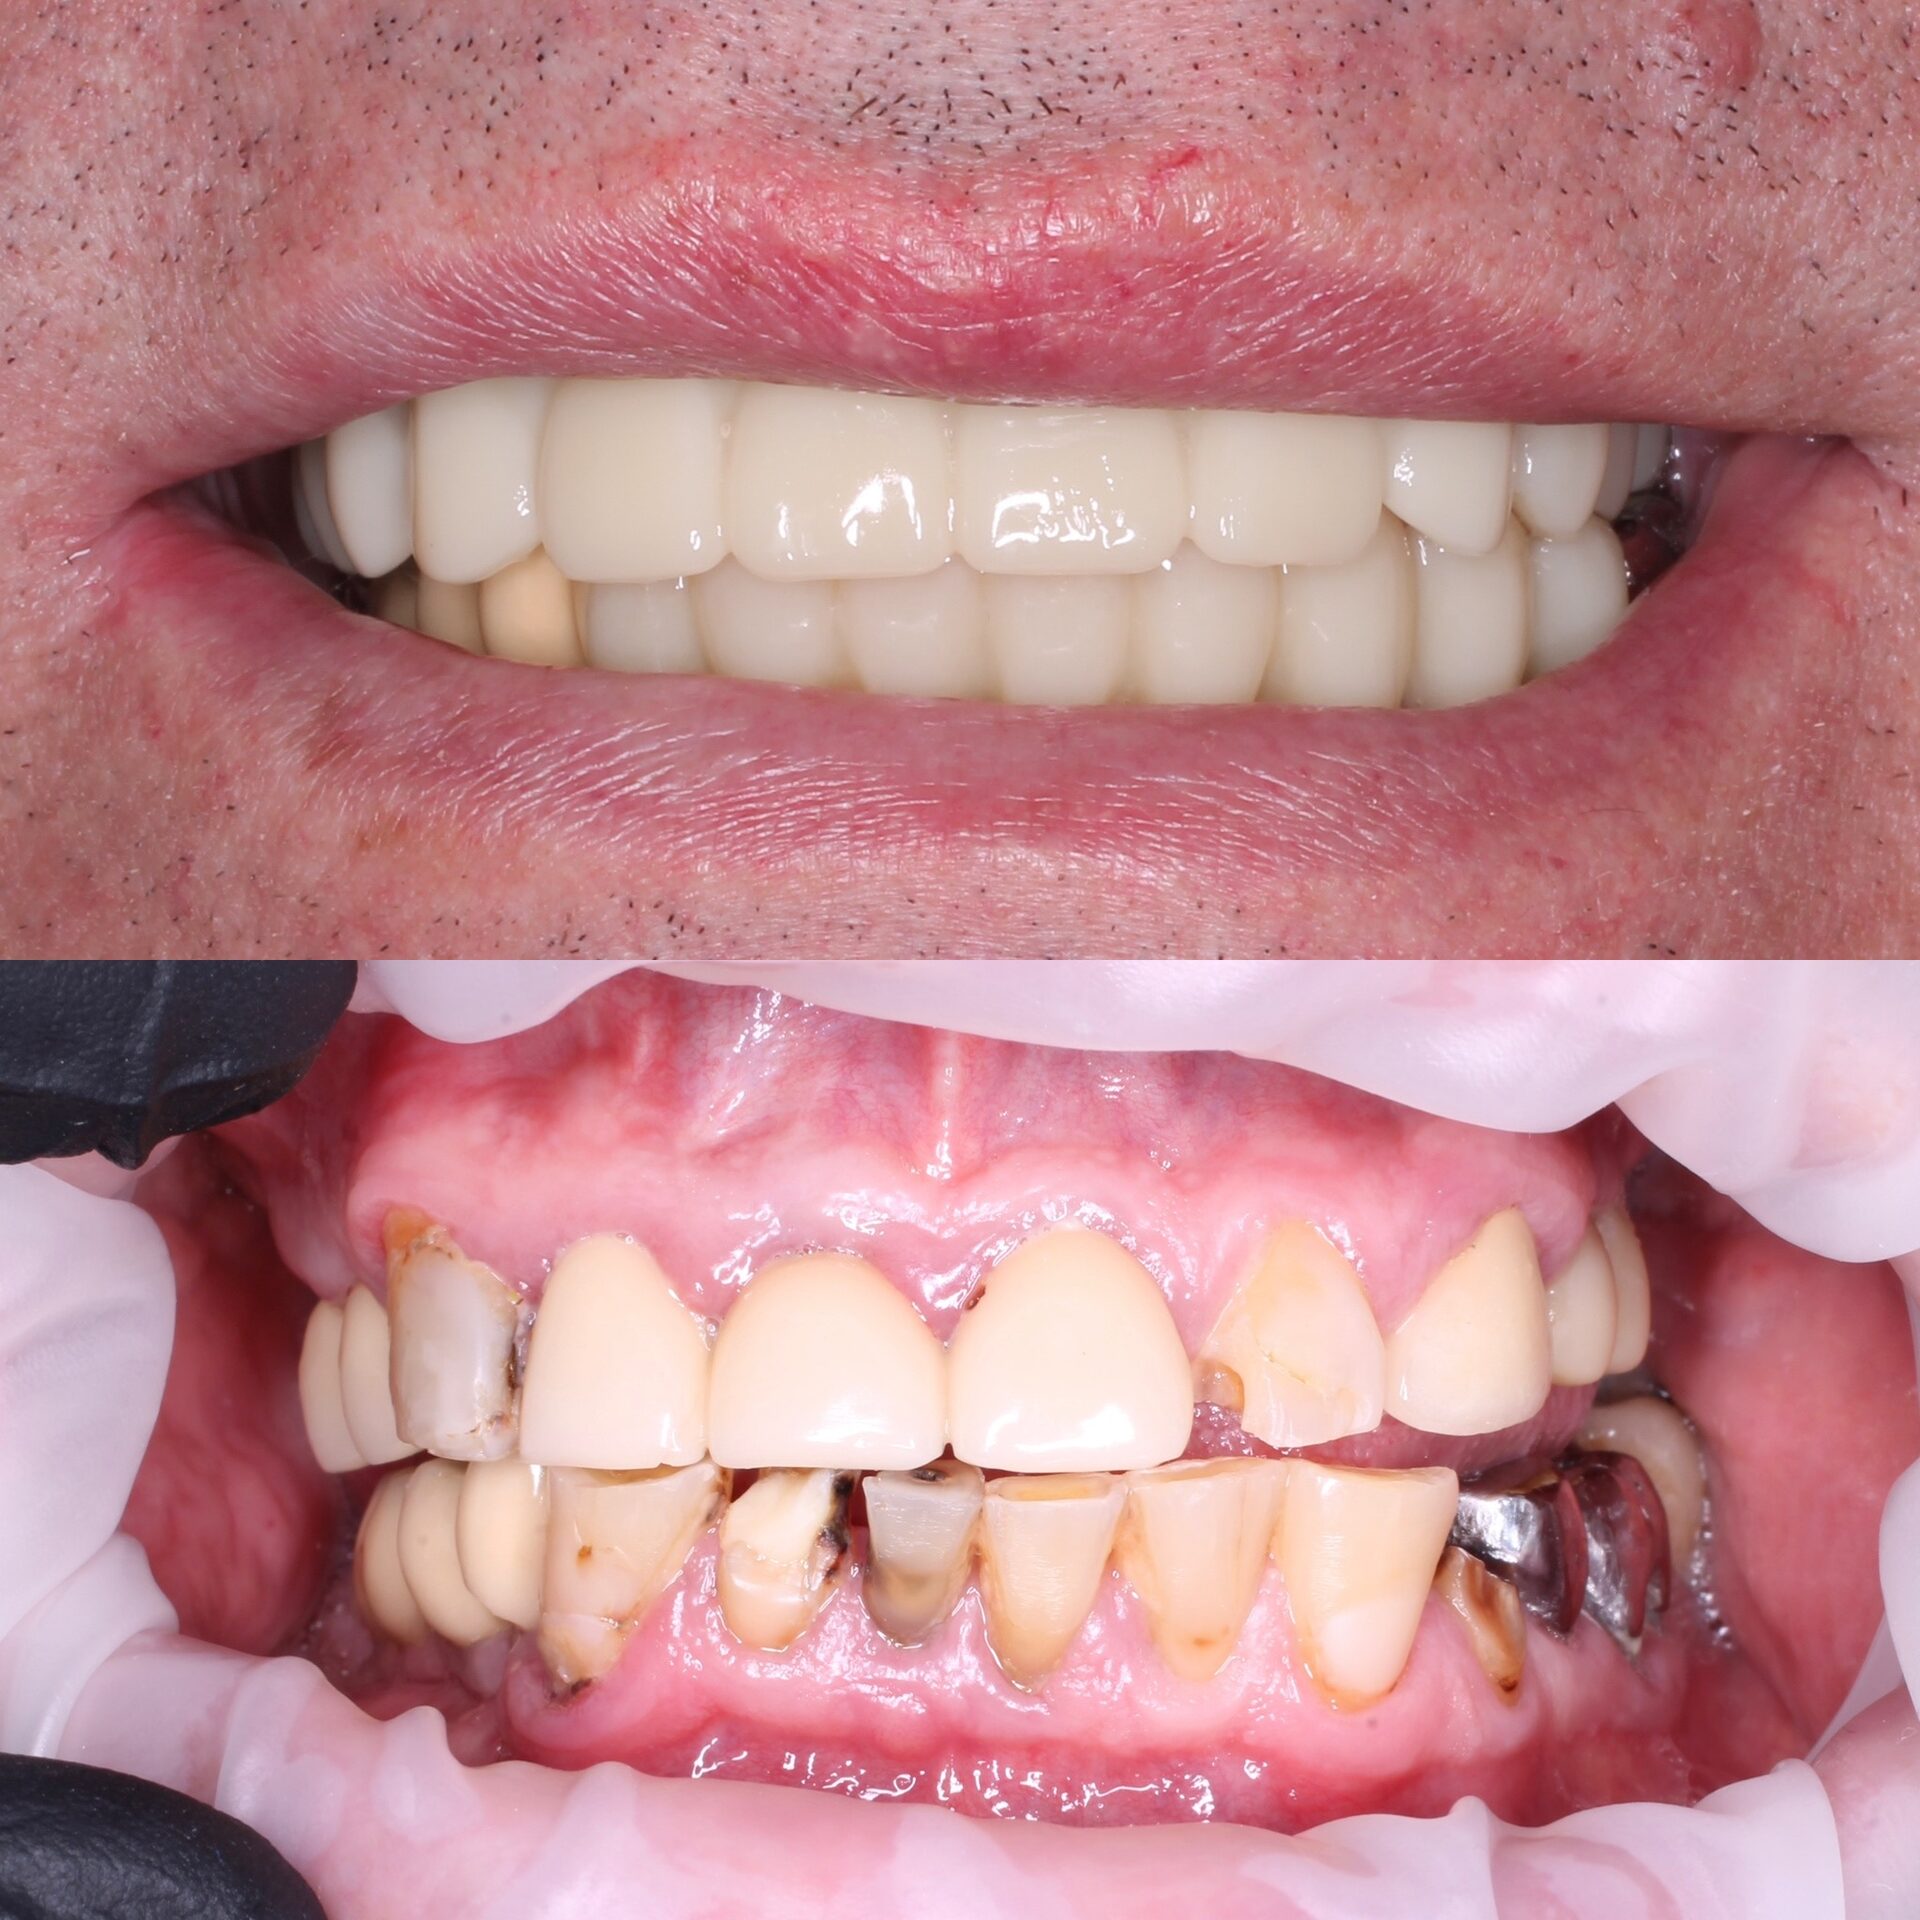

Тотальная реабилитация на 5 имплантатах с фиксацией постоянного керамического протеза на титановой балке